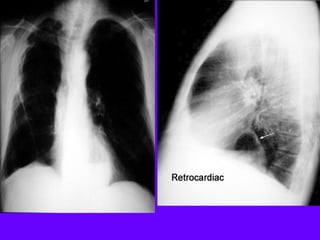

Dissecting Aneurysm

Mediastinal widening

Inlet to outlet shadow

on left side

Retrocardiac: Intact

silhouette of left heart

margin

Pulmonary artery

overlay sign: Density

behind left lower lobe

Wavy margin